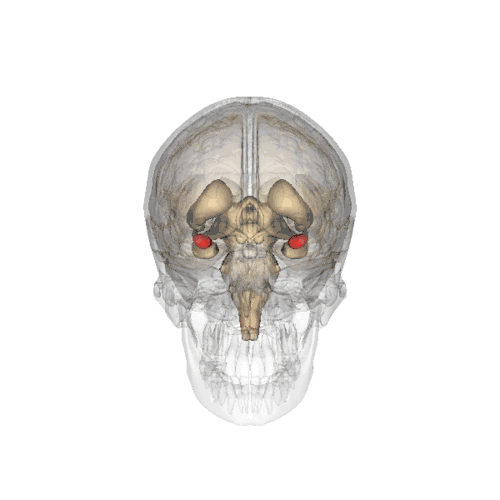

Amygdala

Die Amygdala oder der Mandelkern ist ein paariges Kerngebiet des Gehirns im zur Mitte gelegenen Teil des jeweiligen Temporallappens. Sie ist Teil des limbischen Systems. Der Name der Amygdala (fachsprachlicher Plural: Amygdalae) ist nach ihrem Aussehen aus lateinisch amygdala, dies aus altgriechisch ἀμυγδάλη ‚Mandel(kern)‘, geschöpft. Sie wird auch als Corpus amygdaloideum bezeichnet.